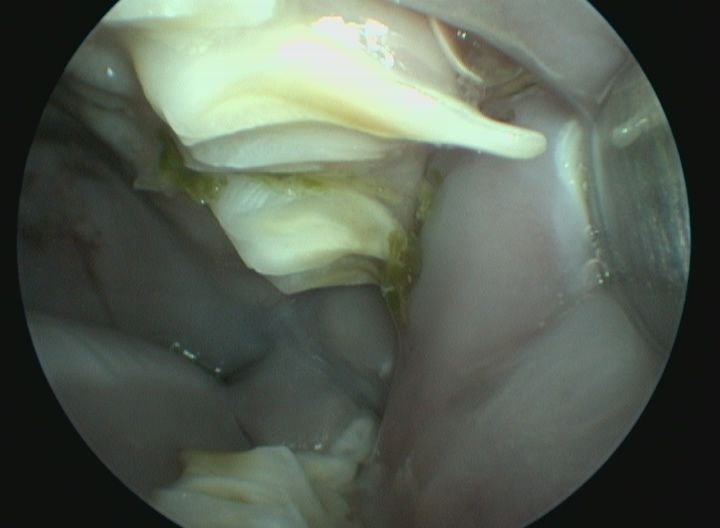

Pour prévenir cette maladie, seule la consommation de foin (foin de Crau ou de phléoles) ou d'herbe fraîche permet l'usure efficace des molaires. Les signes de malocclusion sont des signes de salivation, de refus de s'alimenter, de l'amaigrissement et l'apparition de sécrétions oculaires. En cas d'infection, on observera l'apparition d'abcès dentaires. Le traitement fait appel à la taille des dents sous anesthésie (appelée parage dentaire) par un vétérinaire spécialisé. Cette taille de dent est, si possible, réalisée à l'aide d'une caméra endoscopique pour examiner les dents localisées dans le fond de la cavité buccale et évaluer des lésions plus discrètes.

Pour déterminer l'origine et les caractéristiques de l'abcès, l'idéal est de réaliser un examen d'imagerie précis comme le scanner. Le scanner correspond à un examen radiographique en trois dimensions. Le traitement de choix est typiquement chirurgical et médical. Certaines de ces chirurgies peuvent être particulièrement complexes et nécessiter l'utilisation d'un endoscope.